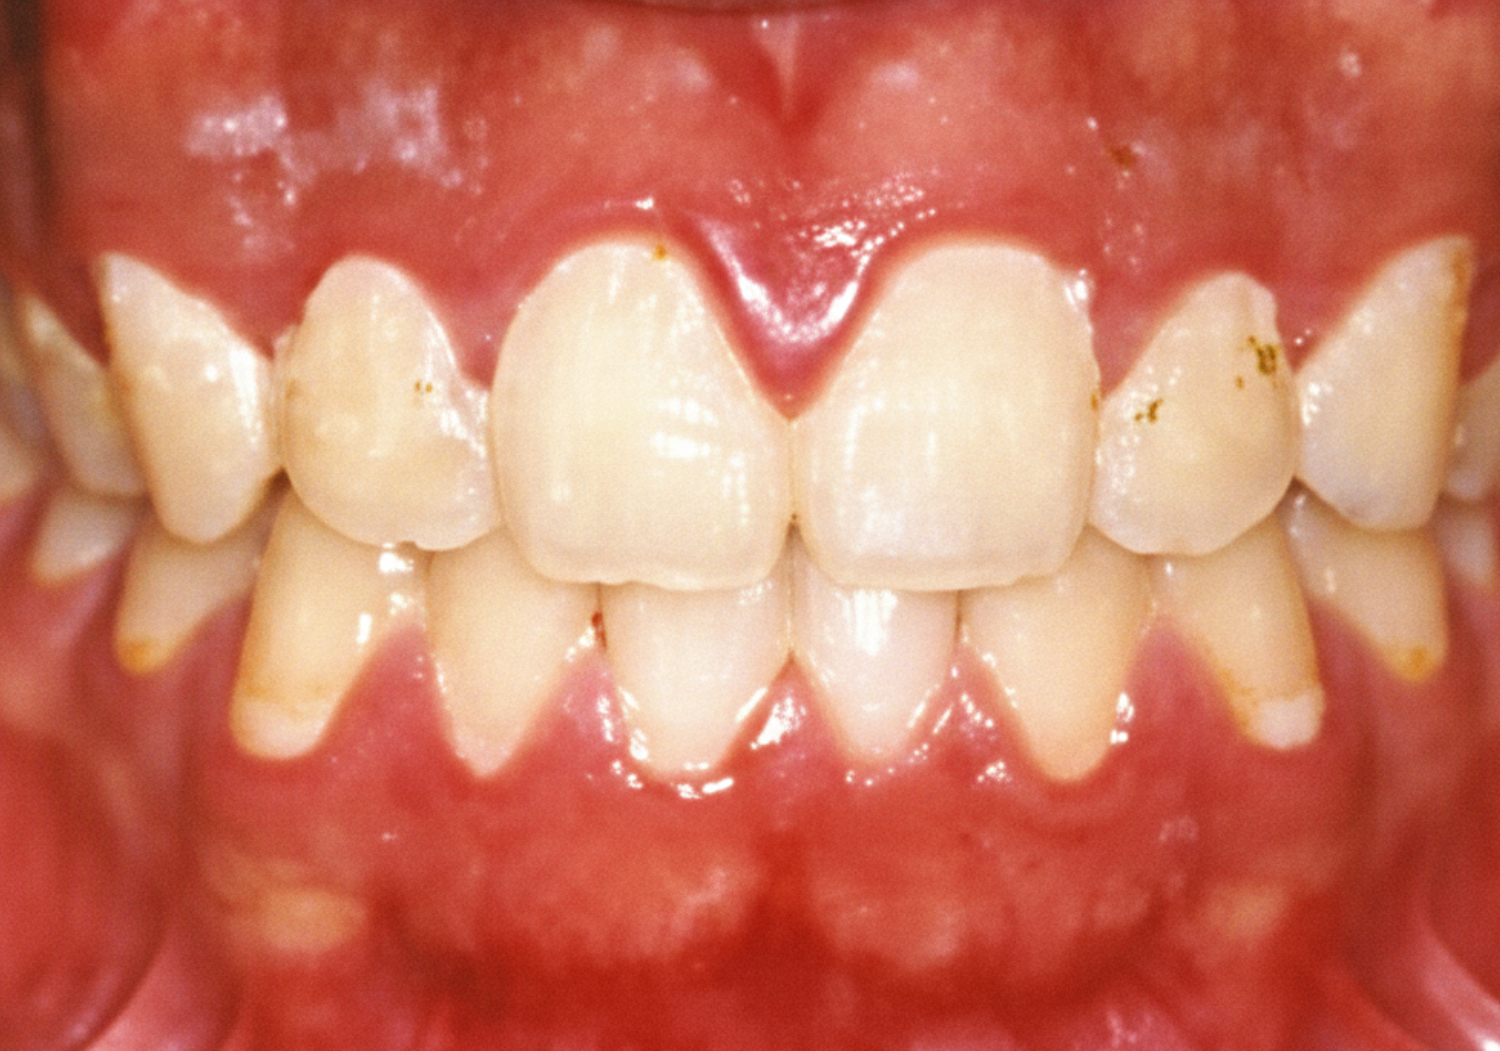

炎症が起きている歯ぐきと

健康的な歯ぐき

▶︎ 改善前

歯石や歯垢がついて歯ぐきが赤く丸くはれています

▶︎ 改善後

歯石をとりご自身でも歯ブラシを適切に行なっていただくことで、歯ぐきが綺麗なピンク色になり、歯ぐきが引き締まってきます

※一般的な歯肉改善の例です